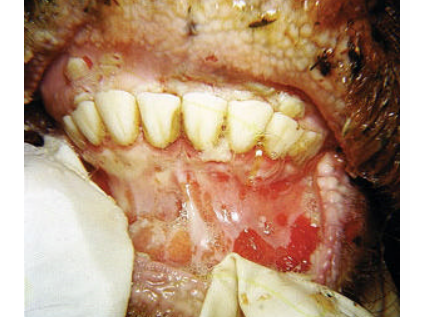

–> Vésicules qui s’ouvrent en ulcères douloureux, notamment dans la bouche, sur les pieds et/ou mamelle ce qui peut entrainer une chute de la lactation.

Quelques exemples de signes cliniques :